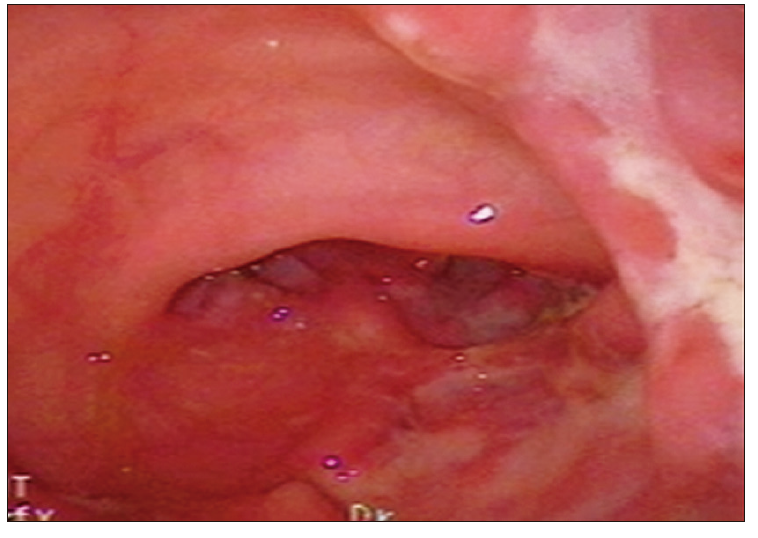

Diferenciar EC de CU: determinadas características de los hallazgos endoscópicos pueden contribuir a la diferenciación entre ambos tipos de EII. La intensidad de los hallazgos guarda relación con la severidad de la actividad mucosa (Tabla 6).

Tabla 6. Patrones endoscópicos diferenciales entre CU y EC

Foto 1. Compromiso asimétrico de la EC